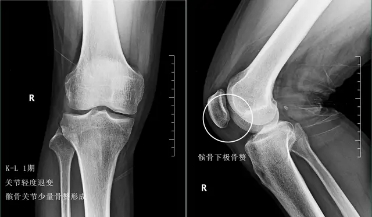

前面已经说到骨关节炎会导致骨赘的形成以及关节间隙的狭窄,所以我们依靠膝关节x片子来初步判断骨关节炎的病情,通常我们采用K_L分期判断病情。

一期患者:患者的关节会开始有轻度的无罪行程,一般这个阶段的患者会有比较明显的上下楼梯的疼痛或者是不适,但是往往走平路反而正常,所以很多这个阶段的患者并没有得到很好的重视。在这个阶段,如果能开始注意保护我们的关节,减轻体重、减少对于关节的使用往往是可以逆转的,但是正是由于症状不是特别的明显,反而很多人忽视了这个病情。